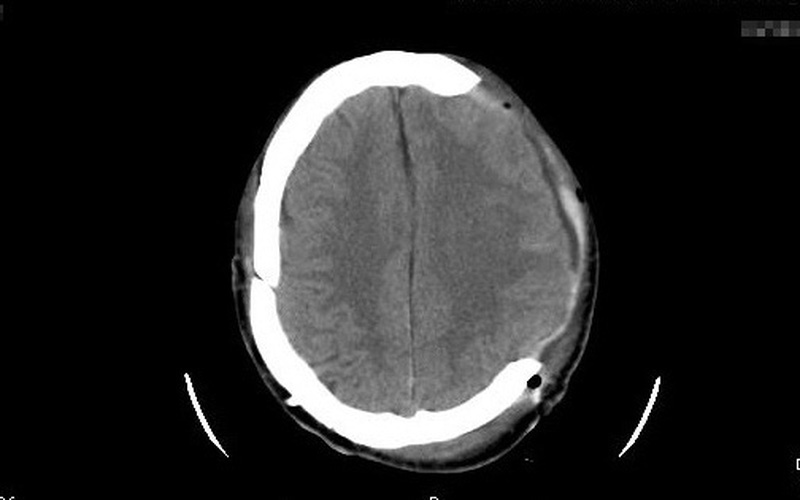

Sau tai nạn, bệnh nhi hôn mê bất tỉnh, chảy máu tai trái, sưng nề vùng đầu, bàn chân trái. Bệnh nhi nhập viện trong tình trạng rất nặng với đa chấn thương, chấn thương sọ não (vỡ xương sọ, dập não) và có nhiều vết thương phần mềm trên cơ thể.

Một trường hợp khác là bệnh nhi 14 tuổi (nam, trú tại Thọ Xuân, Thanh Hóa) khi đang điều khiển xe máy, bệnh nhi không may va chạm với xe ô tô tải (không ai chứng kiến). Sau tai nạn, bệnh nhi kích thích, la hét nhiều, chảy máu mũi 2 bên, vùng đỉnh đầu sưng nề bầm tím.

Bệnh nhi nhanh chóng được đưa vào bệnh viện huyện cấp cứu và chuyển đến Bệnh viện Nhi Thanh Hóa ngay sau đó với tổn thương nội sọ.

Chấn thương sọ não với đa dạng hình thái với nhiều mức độ, từ tụ máu dưới da đầu đến nặng hơn như là các tổn thương ở xương sọ như nứt xương, lún xương sọ hay vết thương sọ não. Nghiêm trọng hơn là các tổn thương chảy máu trong nội sọ phức tạp gây phù não và chèn ép vào các khu vực quan trọng của cơ thể gây tử vong tức thì.